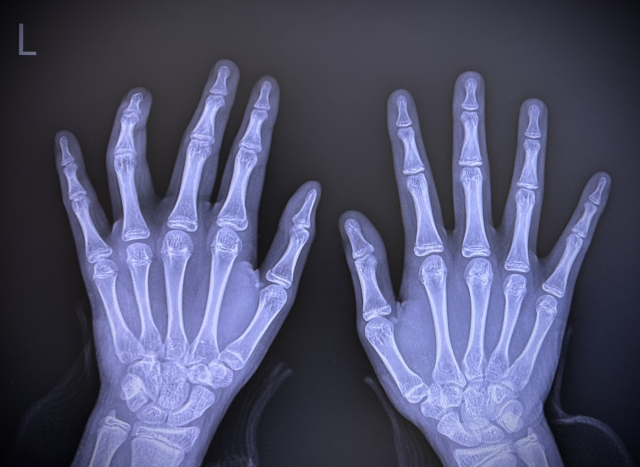

手のレントゲン写真

MD法は、X線を用いて手の骨を撮影し、厚さの異なるアルミニウム板と比較することで骨の状態を評価する検査方法です。骨とアルミニウムの濃度差をもとに、骨密度の目安を算出します。

比較的簡便に測定できるため、DXA(デキサ)装置を備えていない医療機関を中心に用いられている検査方法です。

メリット:ベッドに横になる必要がなく、短時間で検査を受けることができます。

デメリット:DXA法と比べると、骨密度の評価精度は限定的となる場合があります。